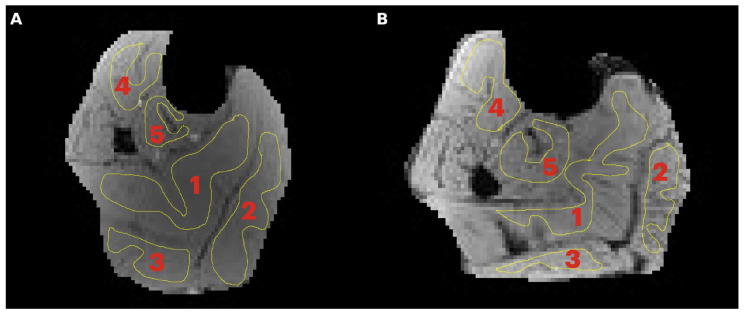

Methods: The lower leg (calf) of 15 young (8M/7F, 25.8 ± 3.7 years) and 9 senior subjects (5F/4M, 68.4 ± 3.3 years) was imaged with the following sequences: multi-offset qMT fit to the Ramani and Yarnykh models, single-offset qMT two-parameter fit to the Ramani model, a semi-quantitative MTsat sequence, magnetization transfer ratio (MTR), and MTR-corrected (MTRcorr) for B1 inhomogeneities. T1 mapping was also performed. Statistical analysis was performed to identify significant age-related and regional (intermuscular) differences.